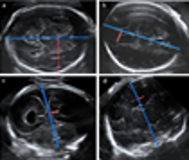

Por la acción de proteínas anormalmente producidas o degradadas, el cerebro no realiza sus funciones, esto da la clasificación de la demencia según la proteína acumulada. También se es causado por la atrofia y dilatación ventricular que se presentan el cual tiene poca relación con lo que se considera demencia o con el deterioro que pueda tener el anciano.